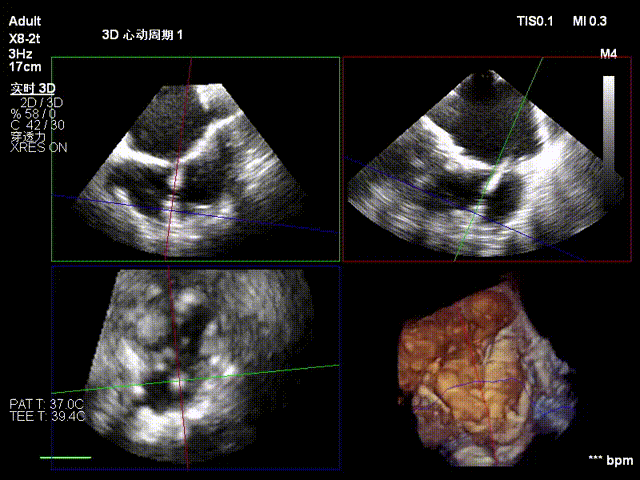

经右颈内静脉穿刺建立通路,置入18Fr鞘管,将K-Clip®输送系统送达右心房。依托三维经食管超声心动图(3D TEE)联合 DSA 双模态引导,经验精准定位瓣环,于后隔交界(P-S commissure)植入14T规格K-Clip®,前后交界(A-P commissure)植入16T规格K-Clip®,实现瓣环多点精准环缩。每枚夹子释放后,团队实时通过超声评估瓣叶对合及反流改善情况,严格遵循 “精准定位 - 锚定验证 - 安全解离” 的规范化操作流程,确认无瓣叶损伤、瓣口狭窄及心包并发症后,完成器械解离与撤出。

5. 第二枚夹子同样操作,三维下夹子形态稳定

术后结果